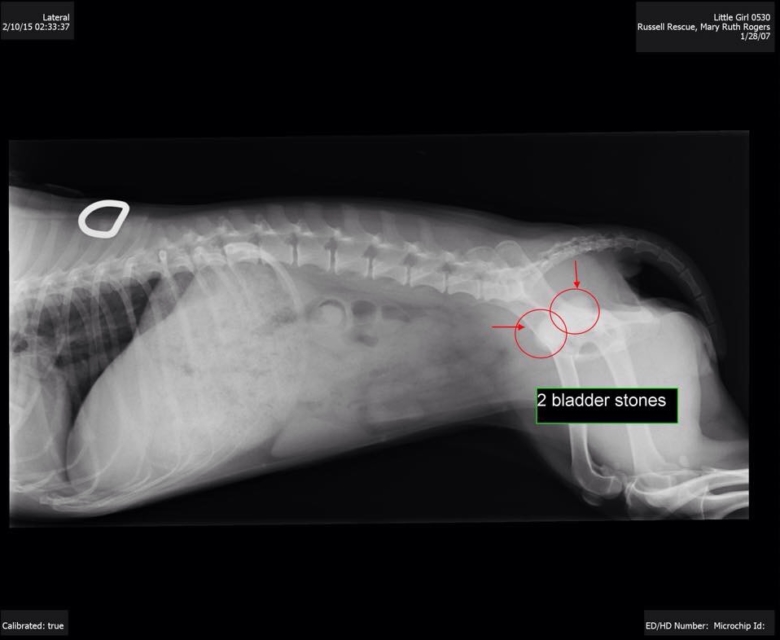

We are often contacted to save dogs that are elderly, are severely injured or neglected, or have special needs or handicaps. We do not refuse these dogs based on medical needs, regardless of the costs of their care. We believe every dog deserves a chance at a happy life.